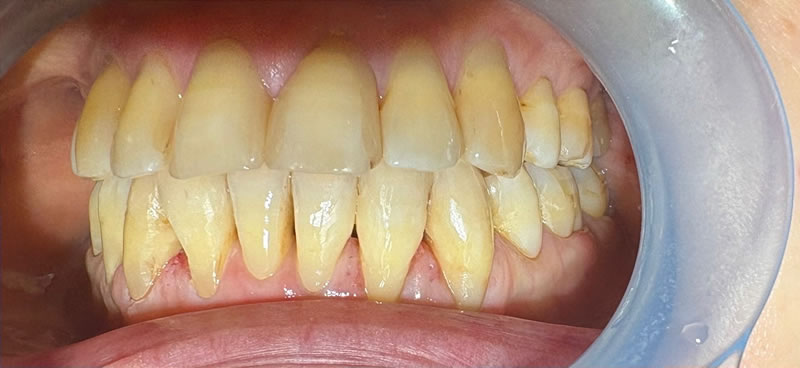

矯正後の60代後半女性で、下の前歯の歯茎下がりの空隙部位に食べものが入ってしまったり唾液が飛ぶから、封鎖したいという主訴でした。

ダイレクトボンディングによる歯の形態修正で足場を作り、ヒアルロン酸をキャリアにした幹細胞由来サイトカインとレーザーによる治癒促進治療による歯周組織再生誘導を同時に併用しました。